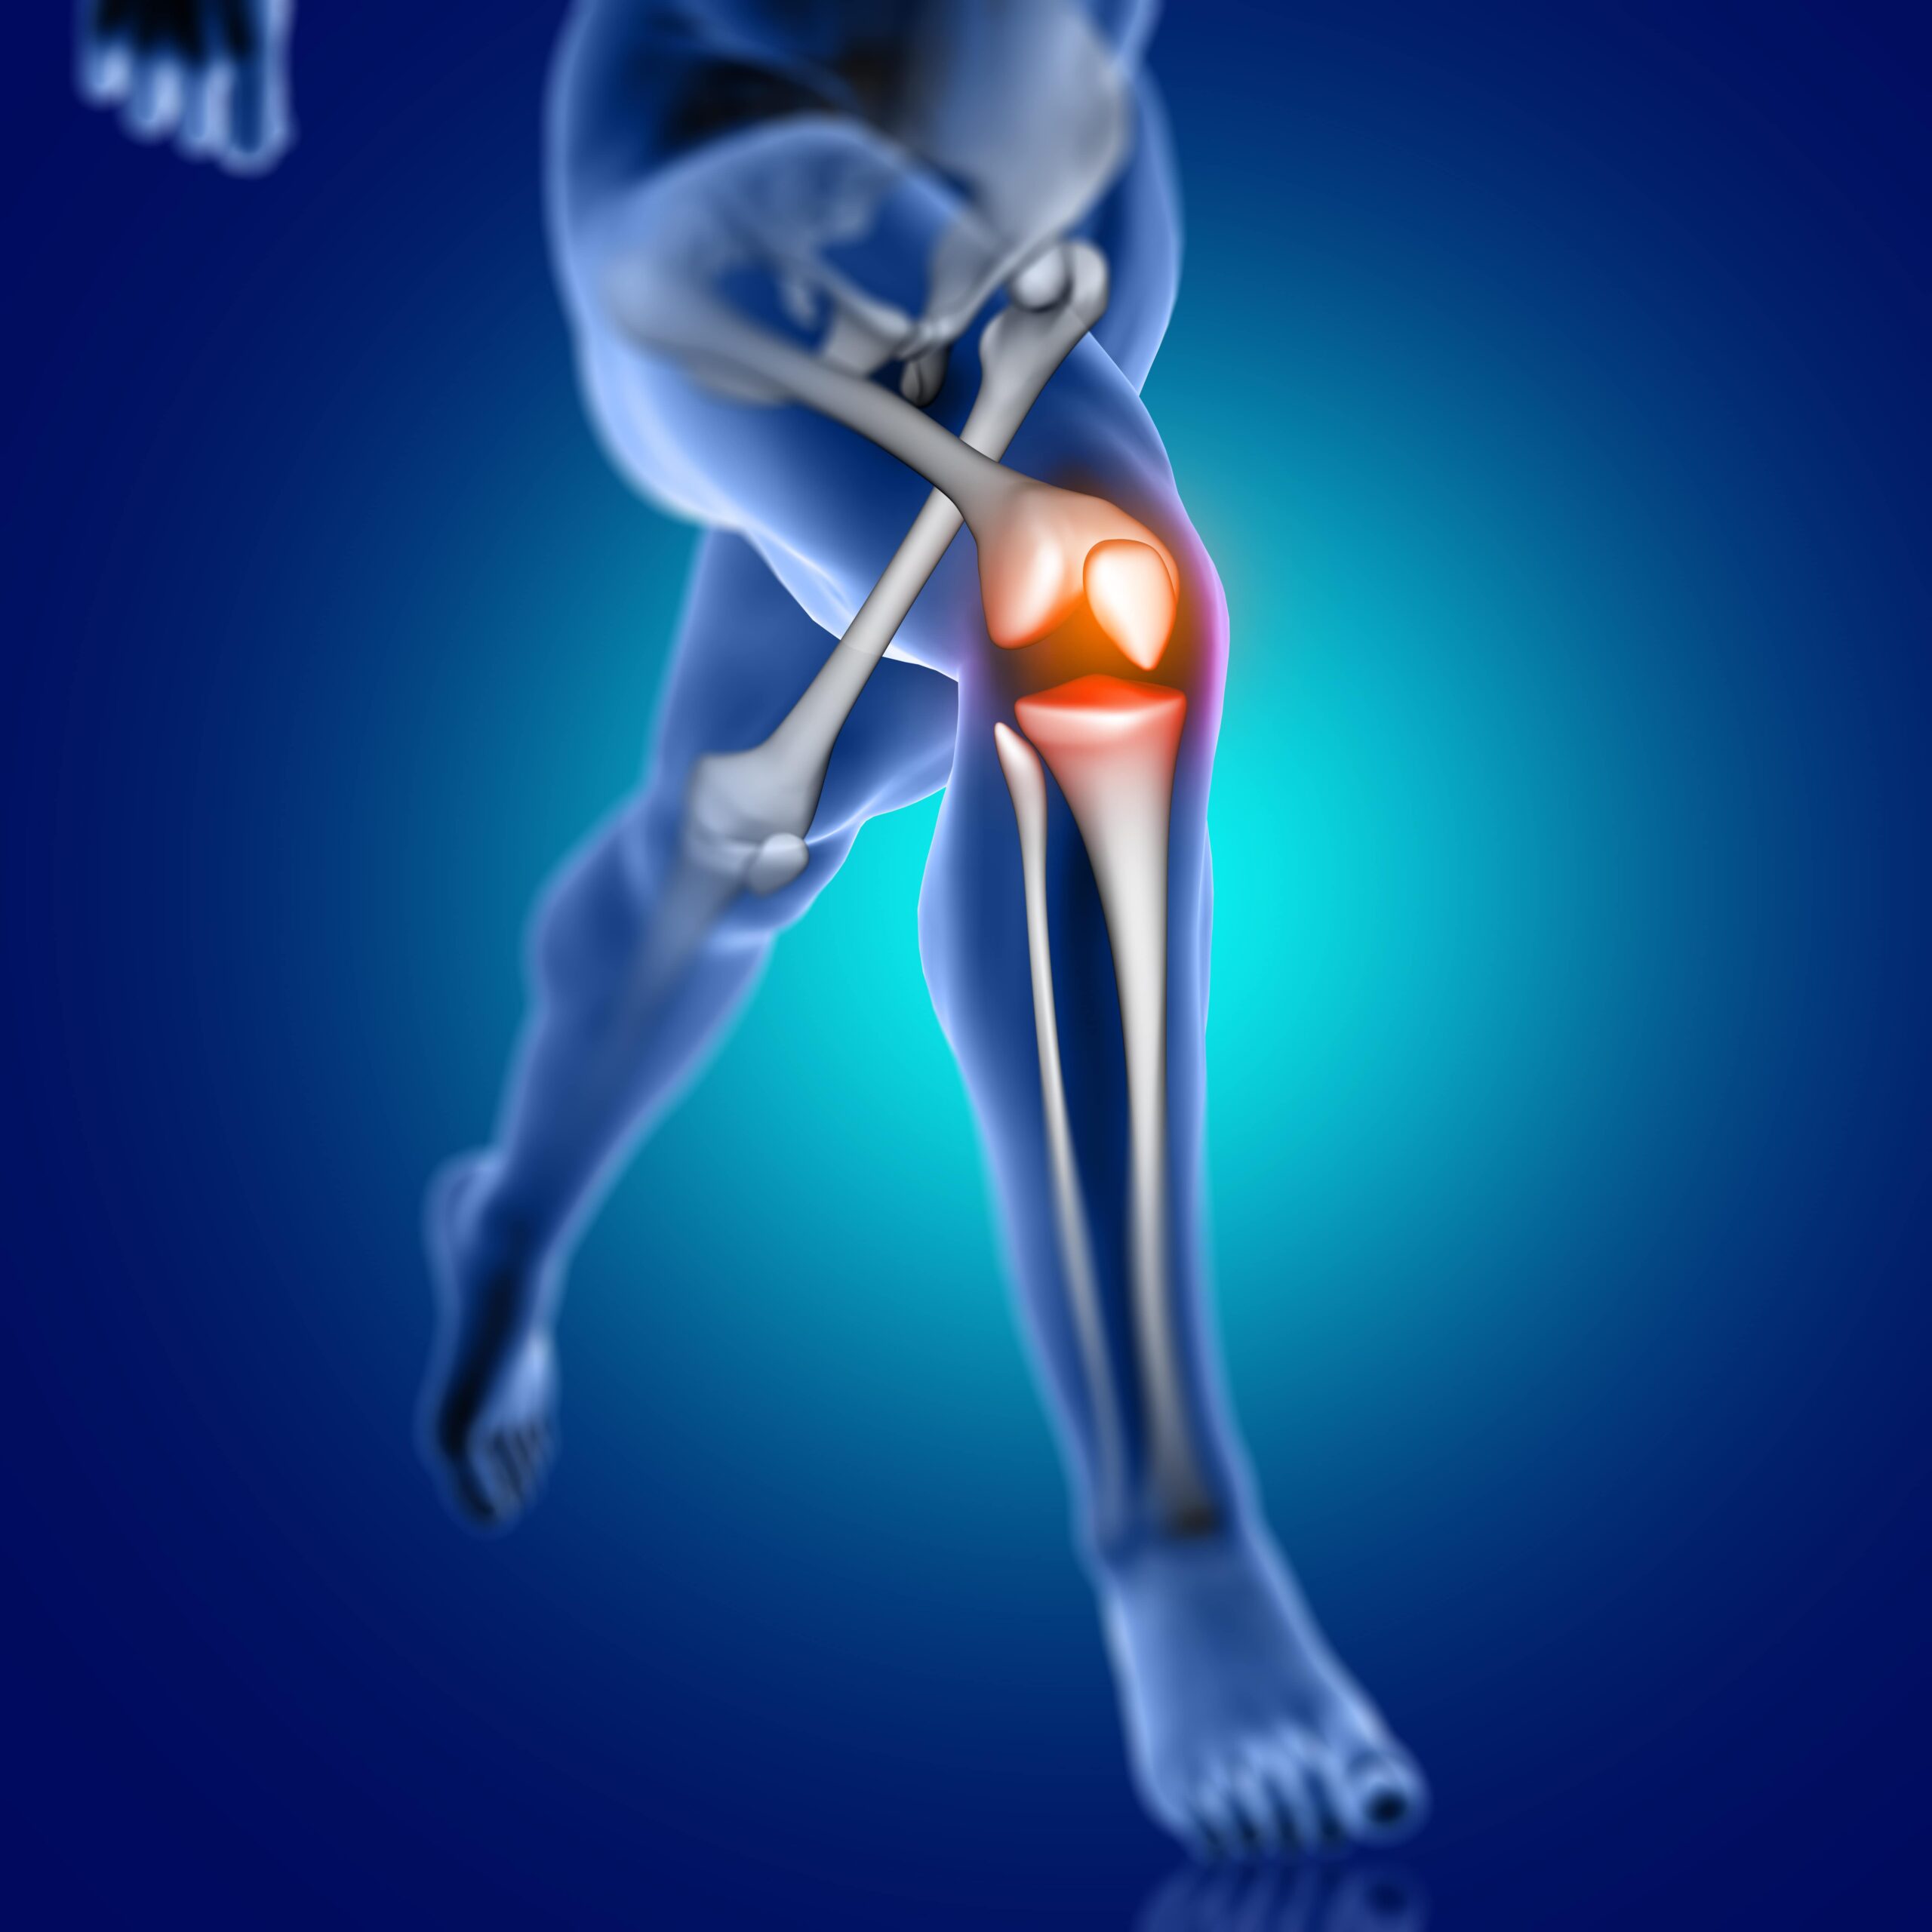

Artroskopi Nedir?

Artroskopi, eklem sorunlarını tanımlamak ve tedavi etmek için kullanılan minimal invazif bir cerrahi işlemdir. Bu yöntem, eklem içi görüntüleme ve cerrahi müdahaleyi bir araya getirerek hastalara daha hızlı iyileşme ve daha az komplikasyon sağlar. Artroskopi sayesinde diz, omuz, dirsek ve diğer eklem sorunları daha etkili bir şekilde tedavi edilebilir.

Artroskopi ile Hangi Eklem Sorunları Tedavi Edilir?

- Dizdeki menisküs yırtıkları

- Dirsekte epitroklea yaralanmaları

- Ayak bileği için endoskopik işlemler

- Omuzdaki rotator manşet yırtıkları

- Ön çapraz bağ yaralanmaları

Artroskopinin Avantajları:

- Minimal invazif bir işlem olduğu için iyileşme süresi kısadır.

- İz bırakmayan küçük kesiler gerektirir.

- Doğrudan eklem içine bakarak doğru teşhis ve tedavi sağlar.

- Eklemdeki sorunları daha büyük cerrahi işlemlere gerek kalmadan çözebilir.

Spor, fiziksel sağlığımızı korumanın ve yaşam kalitemizi artırmanın harika bir yoludur. Ancak bazen spor sırasında veya sonrasında yaşadığımız yaralanmalar, hayatımızı olumsuz etkileyebilir. İşte bu noktada spor cerrahisi devreye girer.